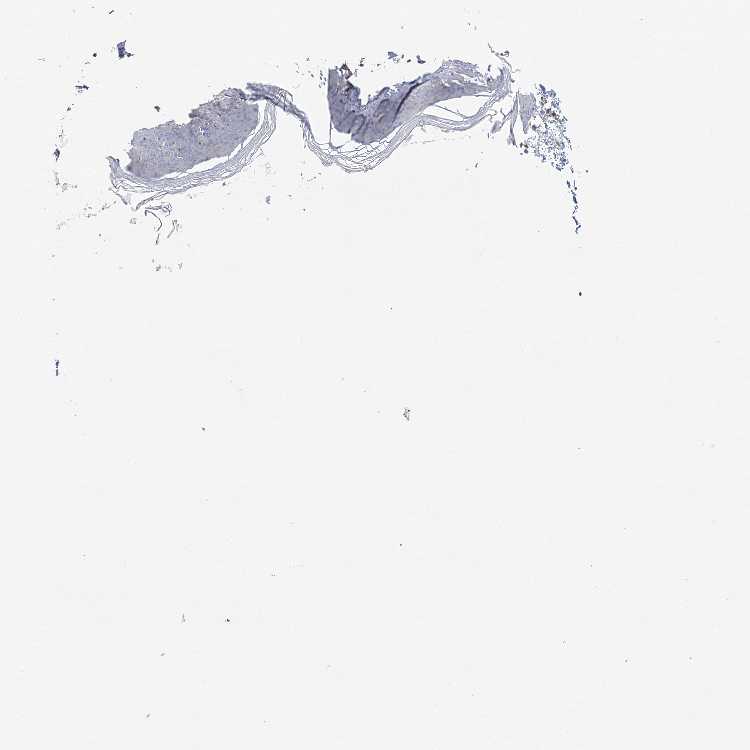

SKIN 1 - Antibody stainingi

Antibody staining in the annotated cell types in the current human tissue is reported as not detected, low, medium, or high, based on conventional immunohistochemistry profiling in selected tissues. This score is based on the combination of the staining intensity and fraction of stained cells.

Each image is clickable and will lead to virtual microscopy that enables deeper exploration of all samples and also displays staining intensity scores, fraction scores and subcellular localization as well as patient and tissue information for each sample.

Antibody HPA037563Antibody HPA037564

Langerhans Not detectedNot detected

Fibroblasts Not detectedNot detected

Keratinocytes LowNot detected

Melanocytes Not detectedNot detected